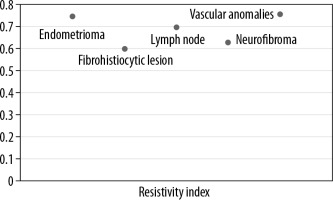

Lipomas, constituting the majority of lesions, were predominantly hyperechoic on conventional ultrasonography, and rest of the lesions were majorly heteroechoic. Doppler assessment was performed to look for the pattern of vascularity and further characteristic parameters, including resistive and pulsatility indices (Figures 1 and 2).

An integrated approach using various ultrasound techniques (greyscale, colour Doppler, and elastography) were performed simultaneously in each case. Conventional ultrasonography was performed following standardised protocols using linear array transducers of frequency 5-17 MHz and 3-9 MHz, and the parameters recorded were location, number, size, shape, echogenicity, and margins for each superficial lesion. Doppler assessment was also done to evaluate the presence or absence of vascularity, pattern of vascularity – whether peripheral or central, and the Doppler parameters (resistivity index, pulsatility index) of the lesions.